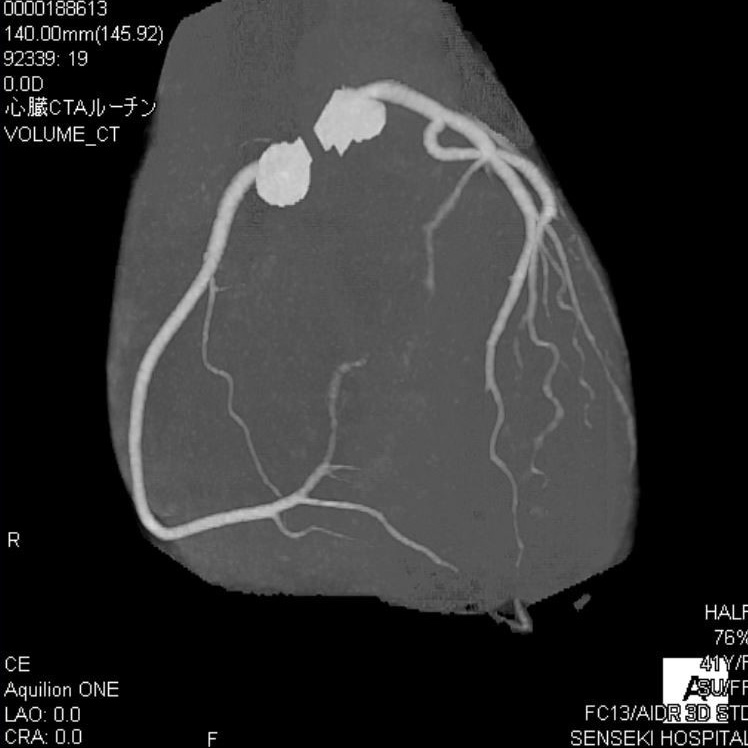

CT室:Aquilion ONE (Canon)・Revolution EVO (GE)

CTとは、X線という放射線を使用して人体の輪切り画像を撮る装置です。その画像を使用して、さまざまな方向の断面像や3Dの画像を再構成をすることもあります。

当院には320列と64列のCTがあります。

■320列CT (Aquilion One)

頭と心臓の検査